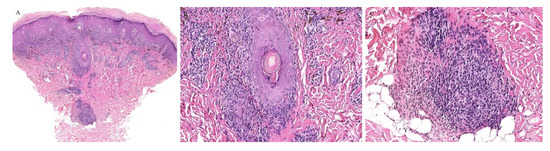

Pityriasis lichenoides (PL) encompasses a variety of dermatoses including the acute ulceronecrotic form, pityriasis lichenoides et varioliformis acuta (PLEVA), as well as pityriasis lichenoides chronica (PLC), which presents as scaly papules and plaques.

Histologically, both forms present with similar findings. Parakeratosis, acanthosis, necrotic keratinocytes, and interface changes are all features of PL. A wedge-shaped perivascular lymphocytic infiltrate can also be seen. The histologic findings of PLEVA are usually more severe than those of PLC [1,2].

Although the inflammatory infiltrate of PL is commonly observed around the blood vessels, adnexotropic variants of PL have been described (Figure 7 and Figure 8). In one retrospective review, adnexotropism was observed in 97% of the specimens studied. It was also found that a denser periadnexal inflammation was observed in PLEVA/PLC overlap cases. This pattern of adnexotropism prompted the authors to suggest the descriptive term of a “T-shaped” inflammatory cell infiltrate, rather than a wedge-shaped infiltrate [37]. Syringotropic lymphocytes has been reported in one case of acral pityriasis lichenoides [38].

Figure 7. (AC) Pityriasis lichenoides et varioliformis acuta with perieccrine inflammation.

Dermatopathology 08 00020 g007

Figure 8. (AC) Pityriasis lichenoides chronica with perieccrine involvement.